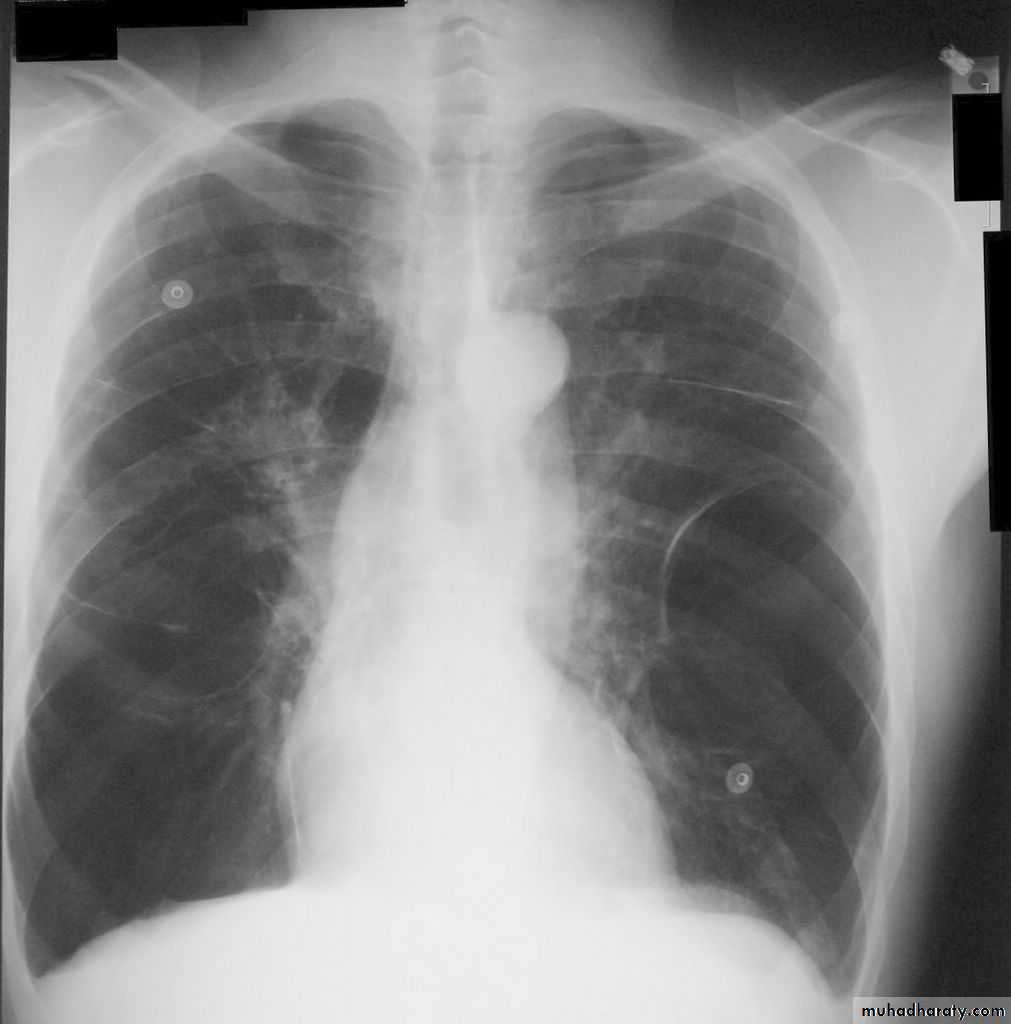

Investigations Imaging

Chest X-ray: Typical changes of emphysema include paucity of parenchymal markings, hyper-translucency and bulae. Increasing lung volume and flattening of diaphragm suggest hyperinflation.